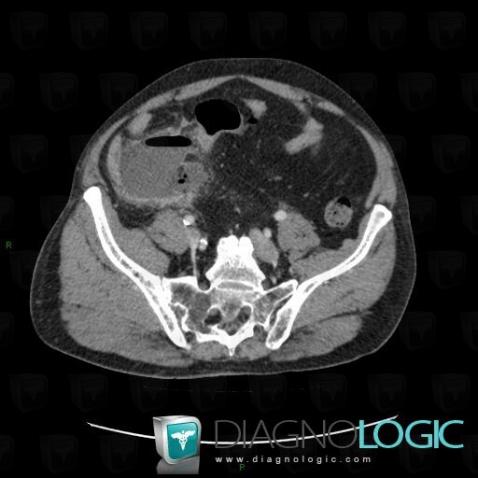

Abscess, Caecum / Appendix, CT

Here is the specific information in the key image above:

- Diagnosis Abscess, Location(s) Caecum / Appendix, with gamuts Appendiceal lesion, Cecal / lleocecal valve lesion, Pericecal fat infitration